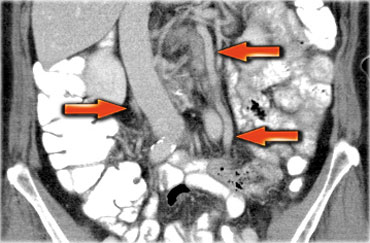

Một phương pháp hữu ích để xác định buồng trứng là theo dõi tĩnh mạch buồng trứng theo hướng đuôi.

Hãy cuộn qua các hình ảnh CT và theo dõi tĩnh mạch buồng trứng phải từ vị trí đổ vào tĩnh mạch chủ dưới, và tĩnh mạch buồng trứng trái từ vị trí đổ vào tĩnh mạch thận trái, cho đến khi xác định được buồng trứng.